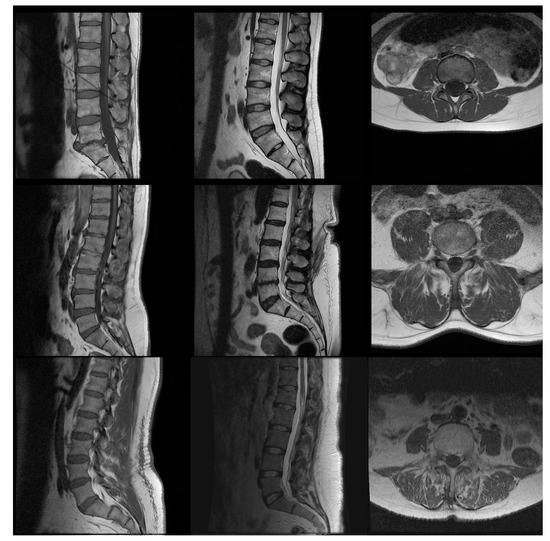

2.1. Data Set

| Exam Type | Criterion Weight | Criterion |

|---|---|---|

| Sagittal | 2/50 | Visualization of vertebral bodies |

| 2/50 | Visualization of spinal cone | |

| 3/50 | Visualization of facet joints | |

| 2/50 | Signal from bone marrow | |

| 5/50 | Overall evaluation | |

| Sagittal | 3/50 | Signal homogeneity in vertebral bodies |

| 1/50 | Visualization of the entrance of basivertebral | |

| venous plexuses | ||

| 3/50 | Contrast between vertebral body and | |

| intervertebral disc | ||

| 3/50 | Spinal cone visualization | |

| 3/50 | Homogeneity of spinal cord signal | |

| 5/50 | Distinction between spinal roots | |

| Axial | 1/50 | Similarity of signal between muscles: |

| paravertebral and psoas | ||

| 5/50 | Definition of the edge of the intervertebral | |

| discs | ||

| 1/50 | Visualization of fascias or grooves of | |

| subcutaneous fat | ||

| 1/50 | Root path through epidural fat | |

| 5/50 | Overall evaluation |